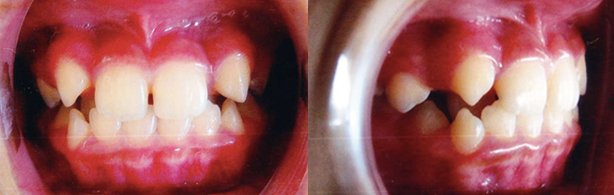

ケース2

治療前

治療後